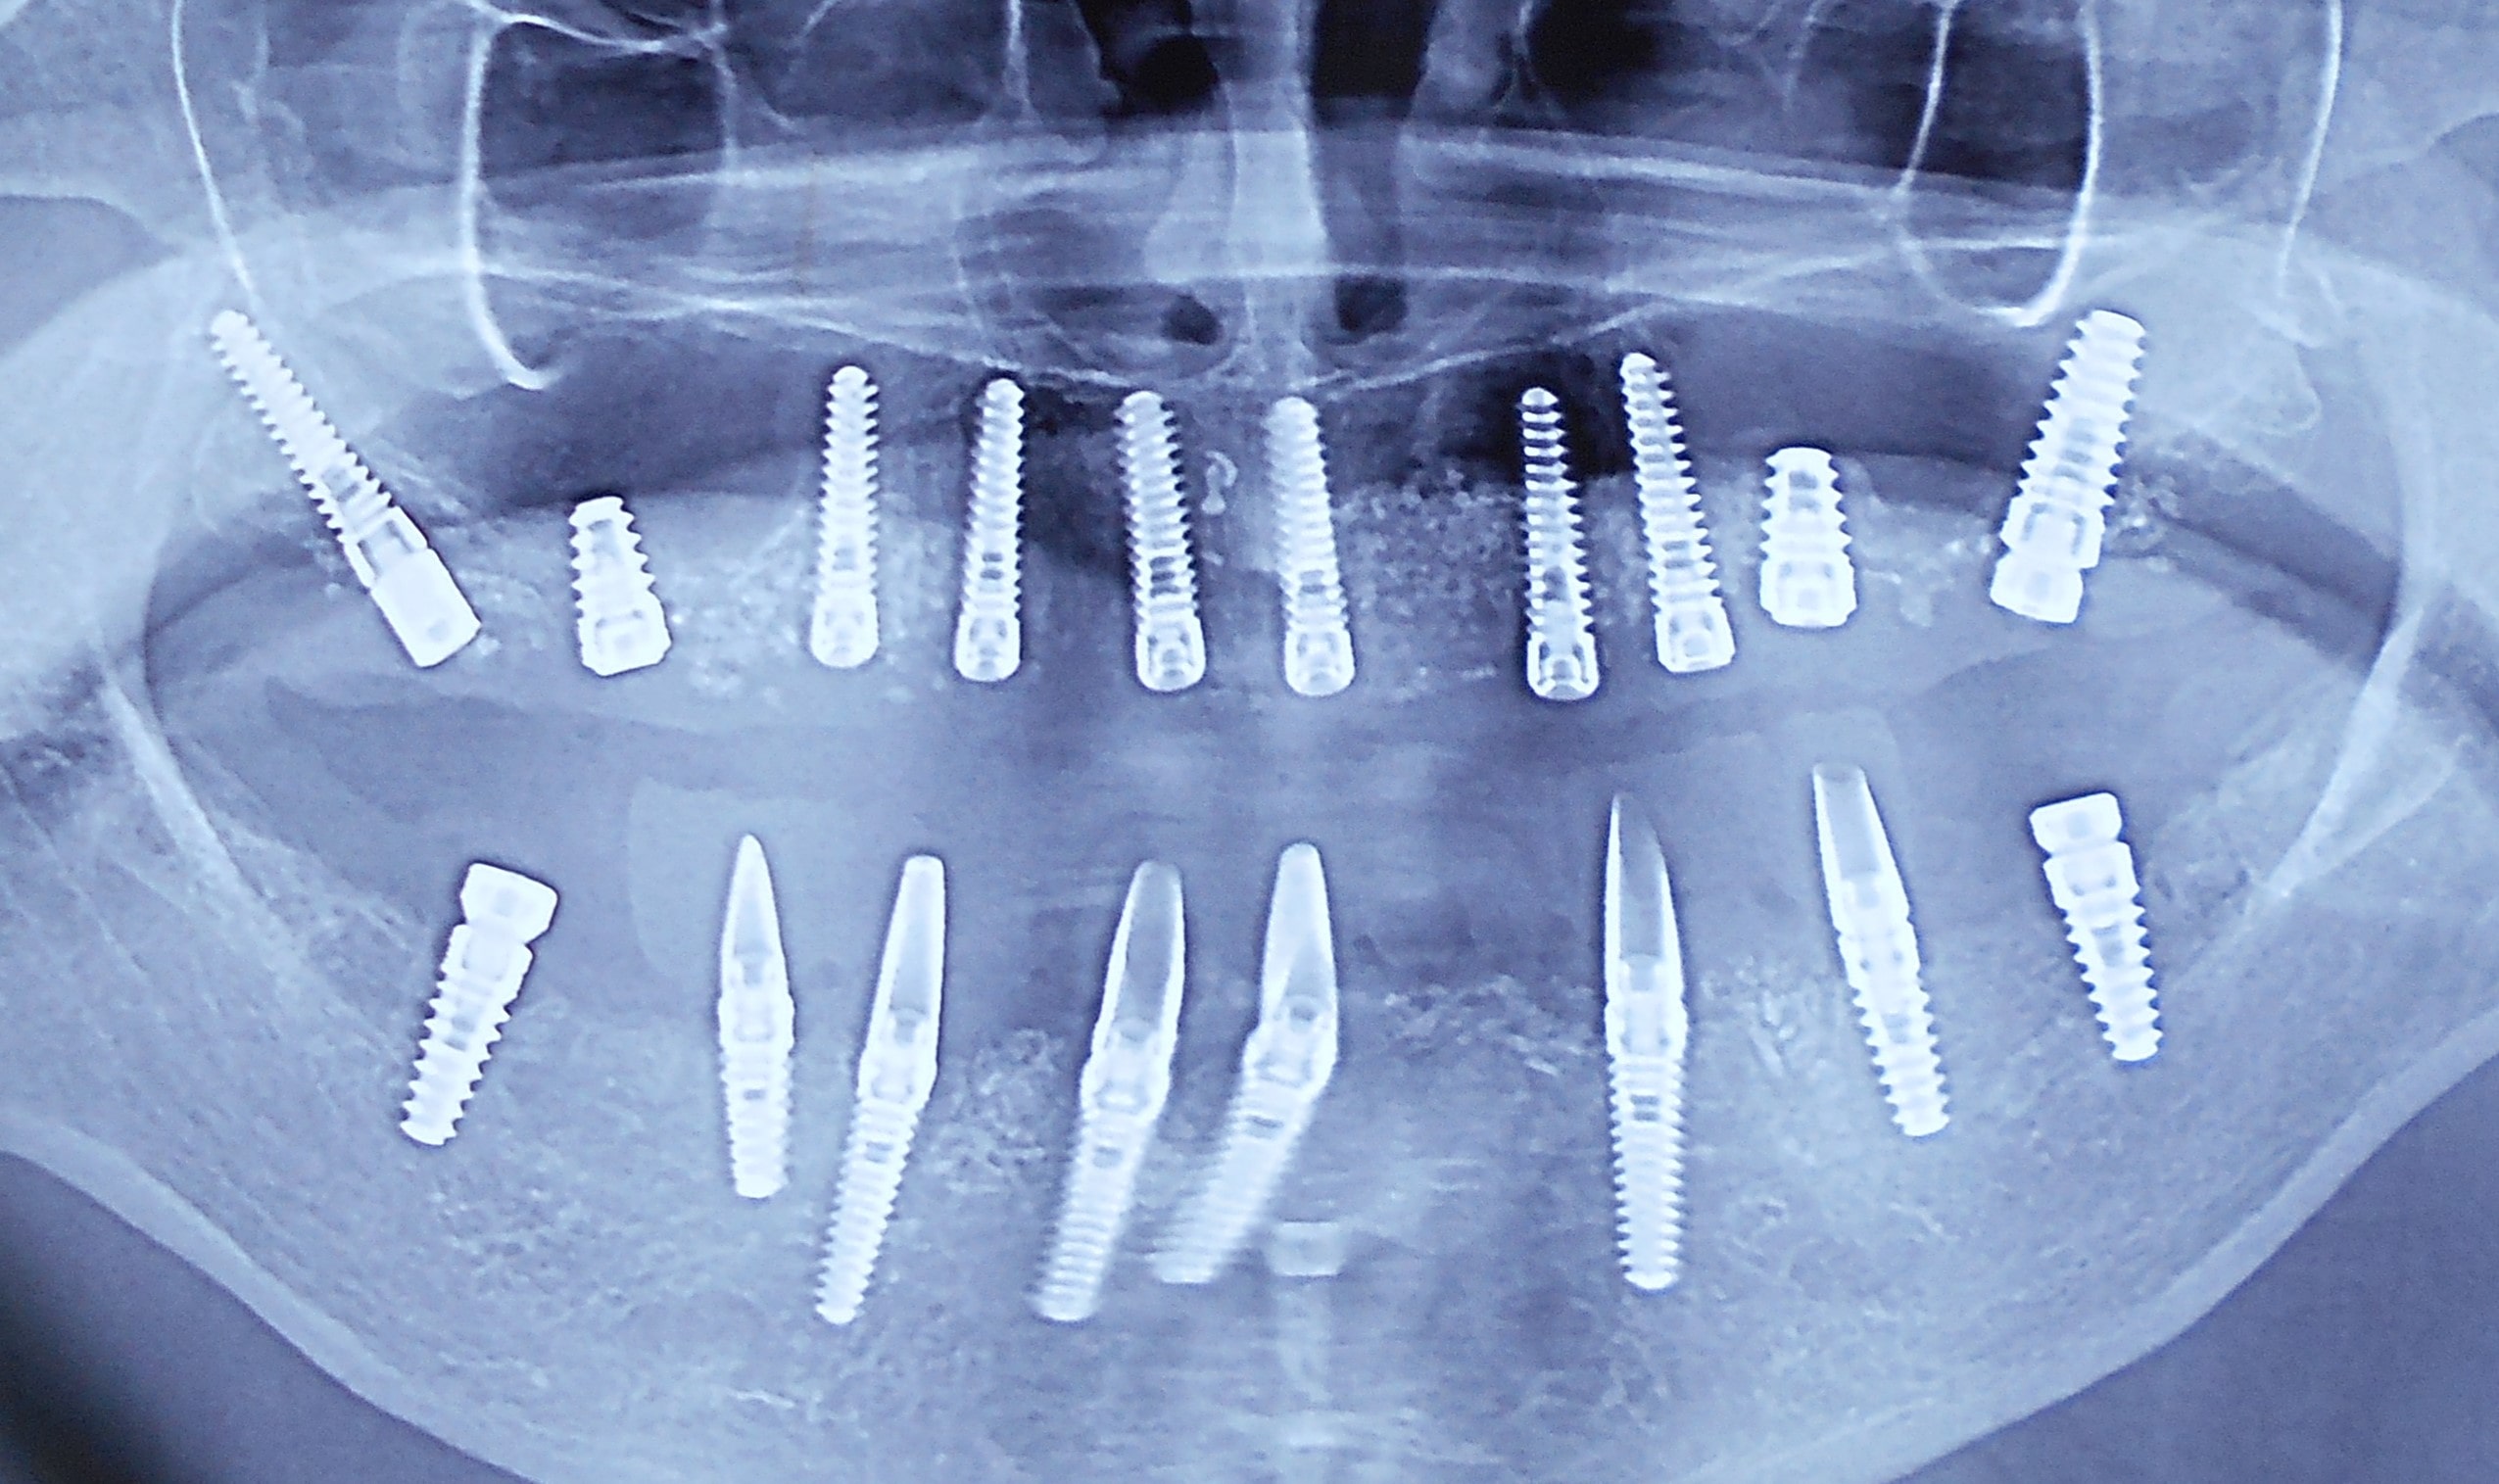

Pacijent dolazi sa starim mostovima i izraženom parodontopatijom u donjoj vilici. Urađeno je skidanje postojećih mostova i istovremena ekstrakcija svih parodontopatičhin zuba uz ugradnju sedam implantata u gornjoj vilici i pet implantata u donjoj vilici. Pacijent je nakon tri dana bio privremneo protetski zbrinut sa fiksnim privremeni krunicama koje su fiksirane na tek ugrađenim implantaima. Nakon četiri meseca je izrađen fiksni cirkonijum kermički- bezmetalni most u gornjoj i donjoj vilici. Rad uspešno završen pre tri godine.

Pacijent iz inostranstva doalzi sa totalnom protezom u gornjoj vilici i sa uznapredovalom parodontopatijom preostalih zuba u donjoj vilici. Pacijent navodi da su mu u inostranstvu rekli da je nemoguće u gornjoj vilici ugraditi implantate bez velikih hirurških zahvata koji podrazumevaju transplantaciju kosti sa udaljenih delova tela i sinus lift proceduru. U gronjoj vilici je bila minimalna količina kosti sa izraženo spuštenim sinusima i sa minimalno vretikalnom i horizontalnom visinom kosti. Naše rešenje se sastojalo u sledećem: ugradnja deset implantata u gornjoj vilici u raspoloživu kost sa ugrdnjom veće količine veštačke kosti, od deset ugrađenih implanta dva implantata su tuberopterigoidna koji su zamenili sinus lift proceduru. U gornjoj vilici smo se opredelili za ugradnju većeg broja implantata kako bi prilikom izrade fiksnog protetskog rada dobili ravnomeran prenos pritiska žvakanja na implantate. U donjoj vilici intervencija je bila istovremena i ona je podrzumevala vađenje svih preostalih zuba i ugradnju osam implantata. Kompletno zbrinjavanje koje obuhvata hiruršku i protetsku fazu je trajalo tri meseca, tokom kojih je pacijent u gornjoj vilici bio zbrinut sa privremenom totalnom protezom, a u donjoj vilici sa fiksnim privremenim zubima koji su bili fiksirani na tek ugrađenim implantatima. Definitivni protetski rad je uspešno završen sa cirkonijum keramičkim - bezmetalnim mostovim pre četiri godine.